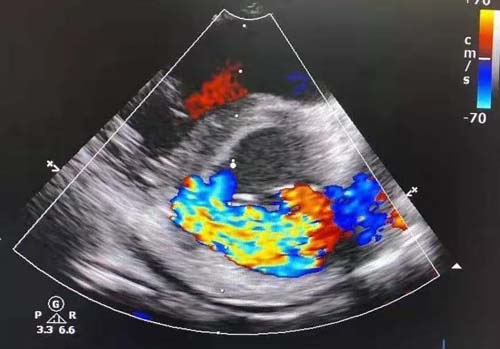

术前超声提示高空坠落伤导致罕见的瓣环撕裂引发二尖瓣严重关闭不全

急症手术在2019年12月26日清晨开始,由邹承伟主任为首的手术团队实施手术。麻醉手术科张孟元主任高度重视,安排主任医师宫本航、主治医师刘希江和王莹组成麻醉团队保障手术进行。患儿入手术室后突然出现呼吸循环衰竭征象,麻醉团队立刻紧急处置,沉着冷静地迅速完成全麻气管插管、动脉穿刺及深静脉穿刺,并采取多种措施进行循环呼吸支持,经及时抢救患儿生命体征逐渐平稳。手术随后开始,术中食道心脏超声由超声诊疗科主任医师郭文彬和朱梅共同完成,经过仔细评估,患儿瓣膜损伤为十分罕见的瓣环撕裂和室间隔夹层,病变导致严重的关闭不全、心腔明显扩张及心脏泵功能衰竭,此种状况,只能通过心外科手术修复。结合超声结果,邹承伟主任、张海洲主任医师和张涛主治医师默契配合,通过精心的设计和精准的操作将受损的瓣膜和室间隔仔细稳妥地修复。很快,患儿的心脏逐渐红润起来,心跳有力,食道心脏超声结果也令人满意,瓣膜修复效果极佳,返流完全消失,手术成功!